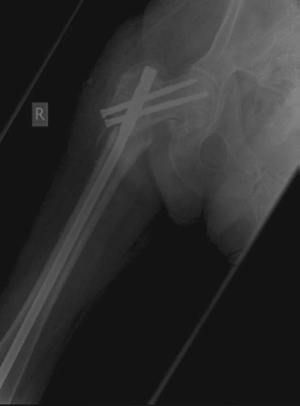

Minute 2 EXAMINER : This woman’s fracture was managed elsewhere and presents during your on-call week with this complication. Can you explain what has happened? (Figures 8.10 and 8.11.) CANDIDATE : This lady was treated with a fixed-angled locking plate. Two things are perhaps responsible for this failure: biomechanics and biology.

Looking at the postoperative radiograph, there is a gap at the fracture site especially medially. The fixed-angled device has been used with locking screws with five screws on either side of the fracture, which will make it a very rigid implant. This will prevent any micro-motion necessary for callus formation. In addition, there is a fracture gap and lack of compression that will preclude primary bone union. This has resulted in a delayed union/atrophic non-union at the fracture site.

The implant has been under constant biomechanical load, which has led to the fatigue failure of the implant. In this particular design there is a stress riser at the junction of the last proximal locking hole and the tapered part of the plate, which dictates the failure point in the implant. In addition, the plating device is applied on the lateral aspect of the femur increasing the lever arm for the moment of force as compared with a cephalomedullary device, which further puts the fixed-angle

Figure 8.10 Anteroposterior (AP) radiograph right femur with fixed locking plate in situ.